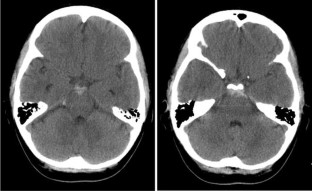

CT scan confirmed P-SAH in both cases. CT angiography in one case and cerebral angiogram in the other did not reveal aneurysm or other potential bleeding source. The patients underwent transcranial Doppler ultrasound monitoring without evidence of vasospasm.

Fig. 1

Fig. 2